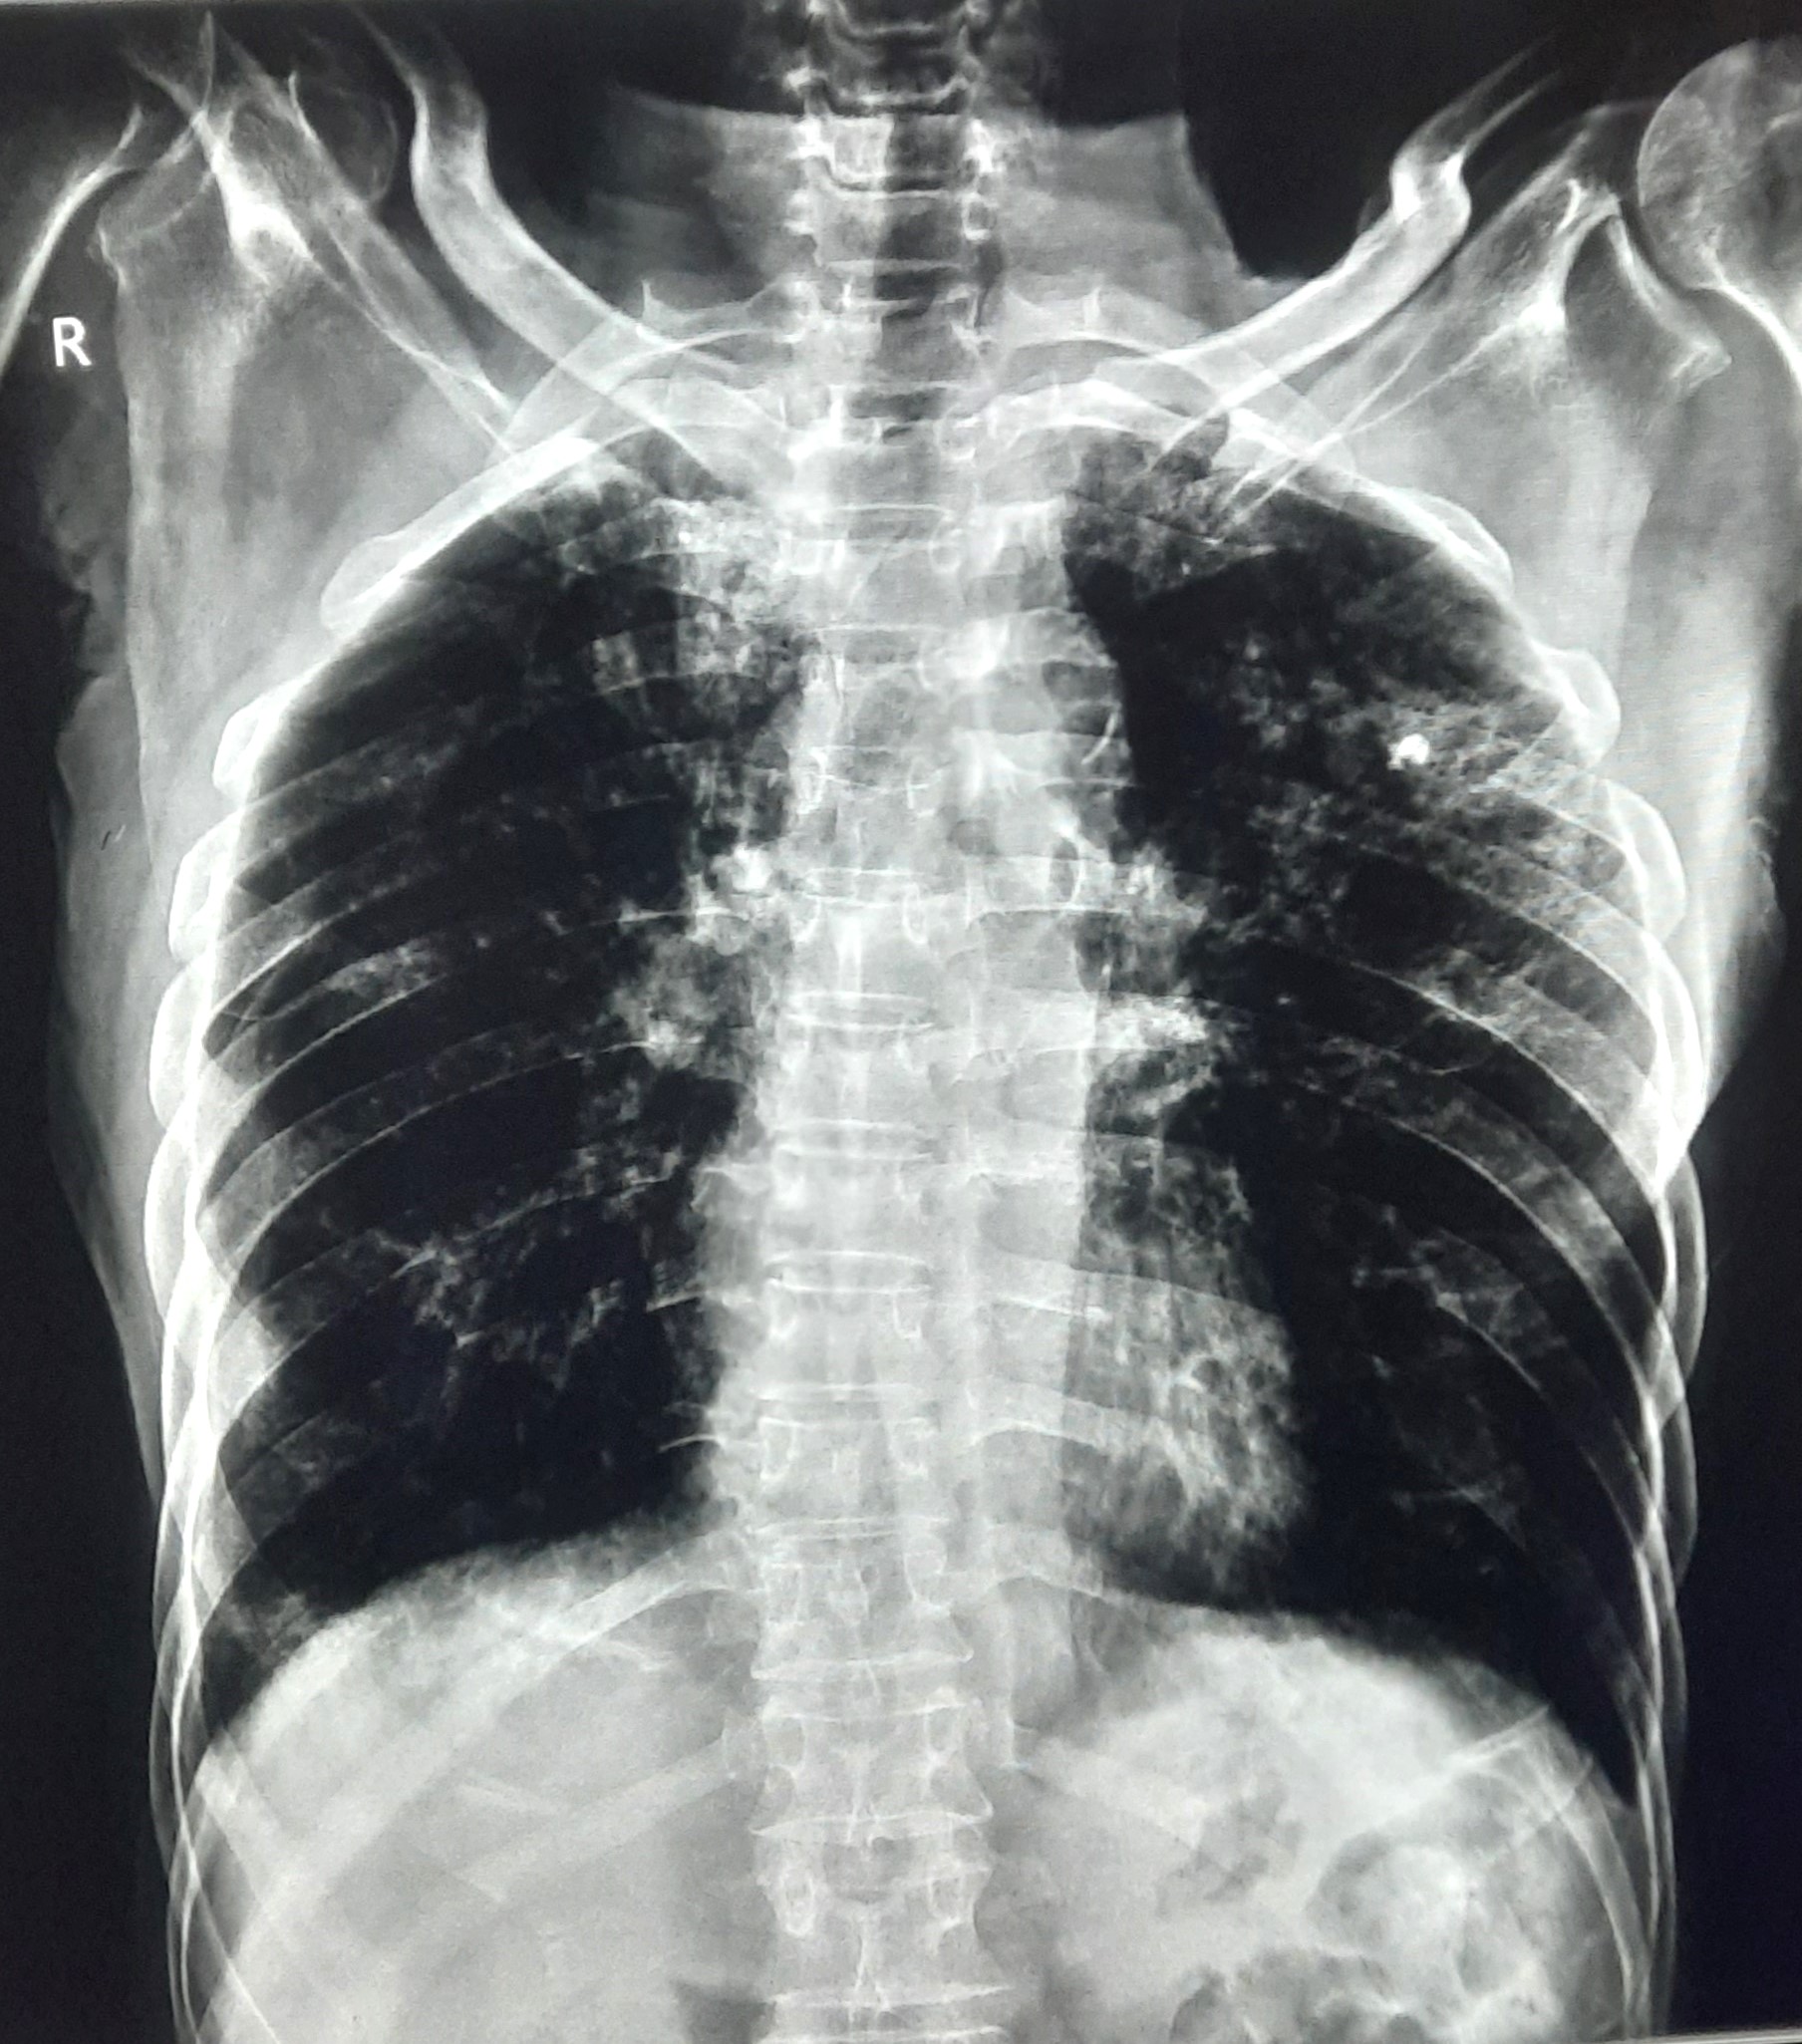

| 102 | IGGMC, Nagpur, Nagpur | P2 | 29-4370 | Prachi Bawane | Consent taken on Paper | 17 Yrs. |

Provisional Diag : PTB?

Final Diag : Active Pulmonary Tuberculosis With Tuberculi? Right Sided Pleural Effusion |

TB Case (Confirmed) | Bilateral ill Defined, No Homogenous Reticulonodular opacities, Right CP Angle Blunting | Abnormality visible on x-ray |